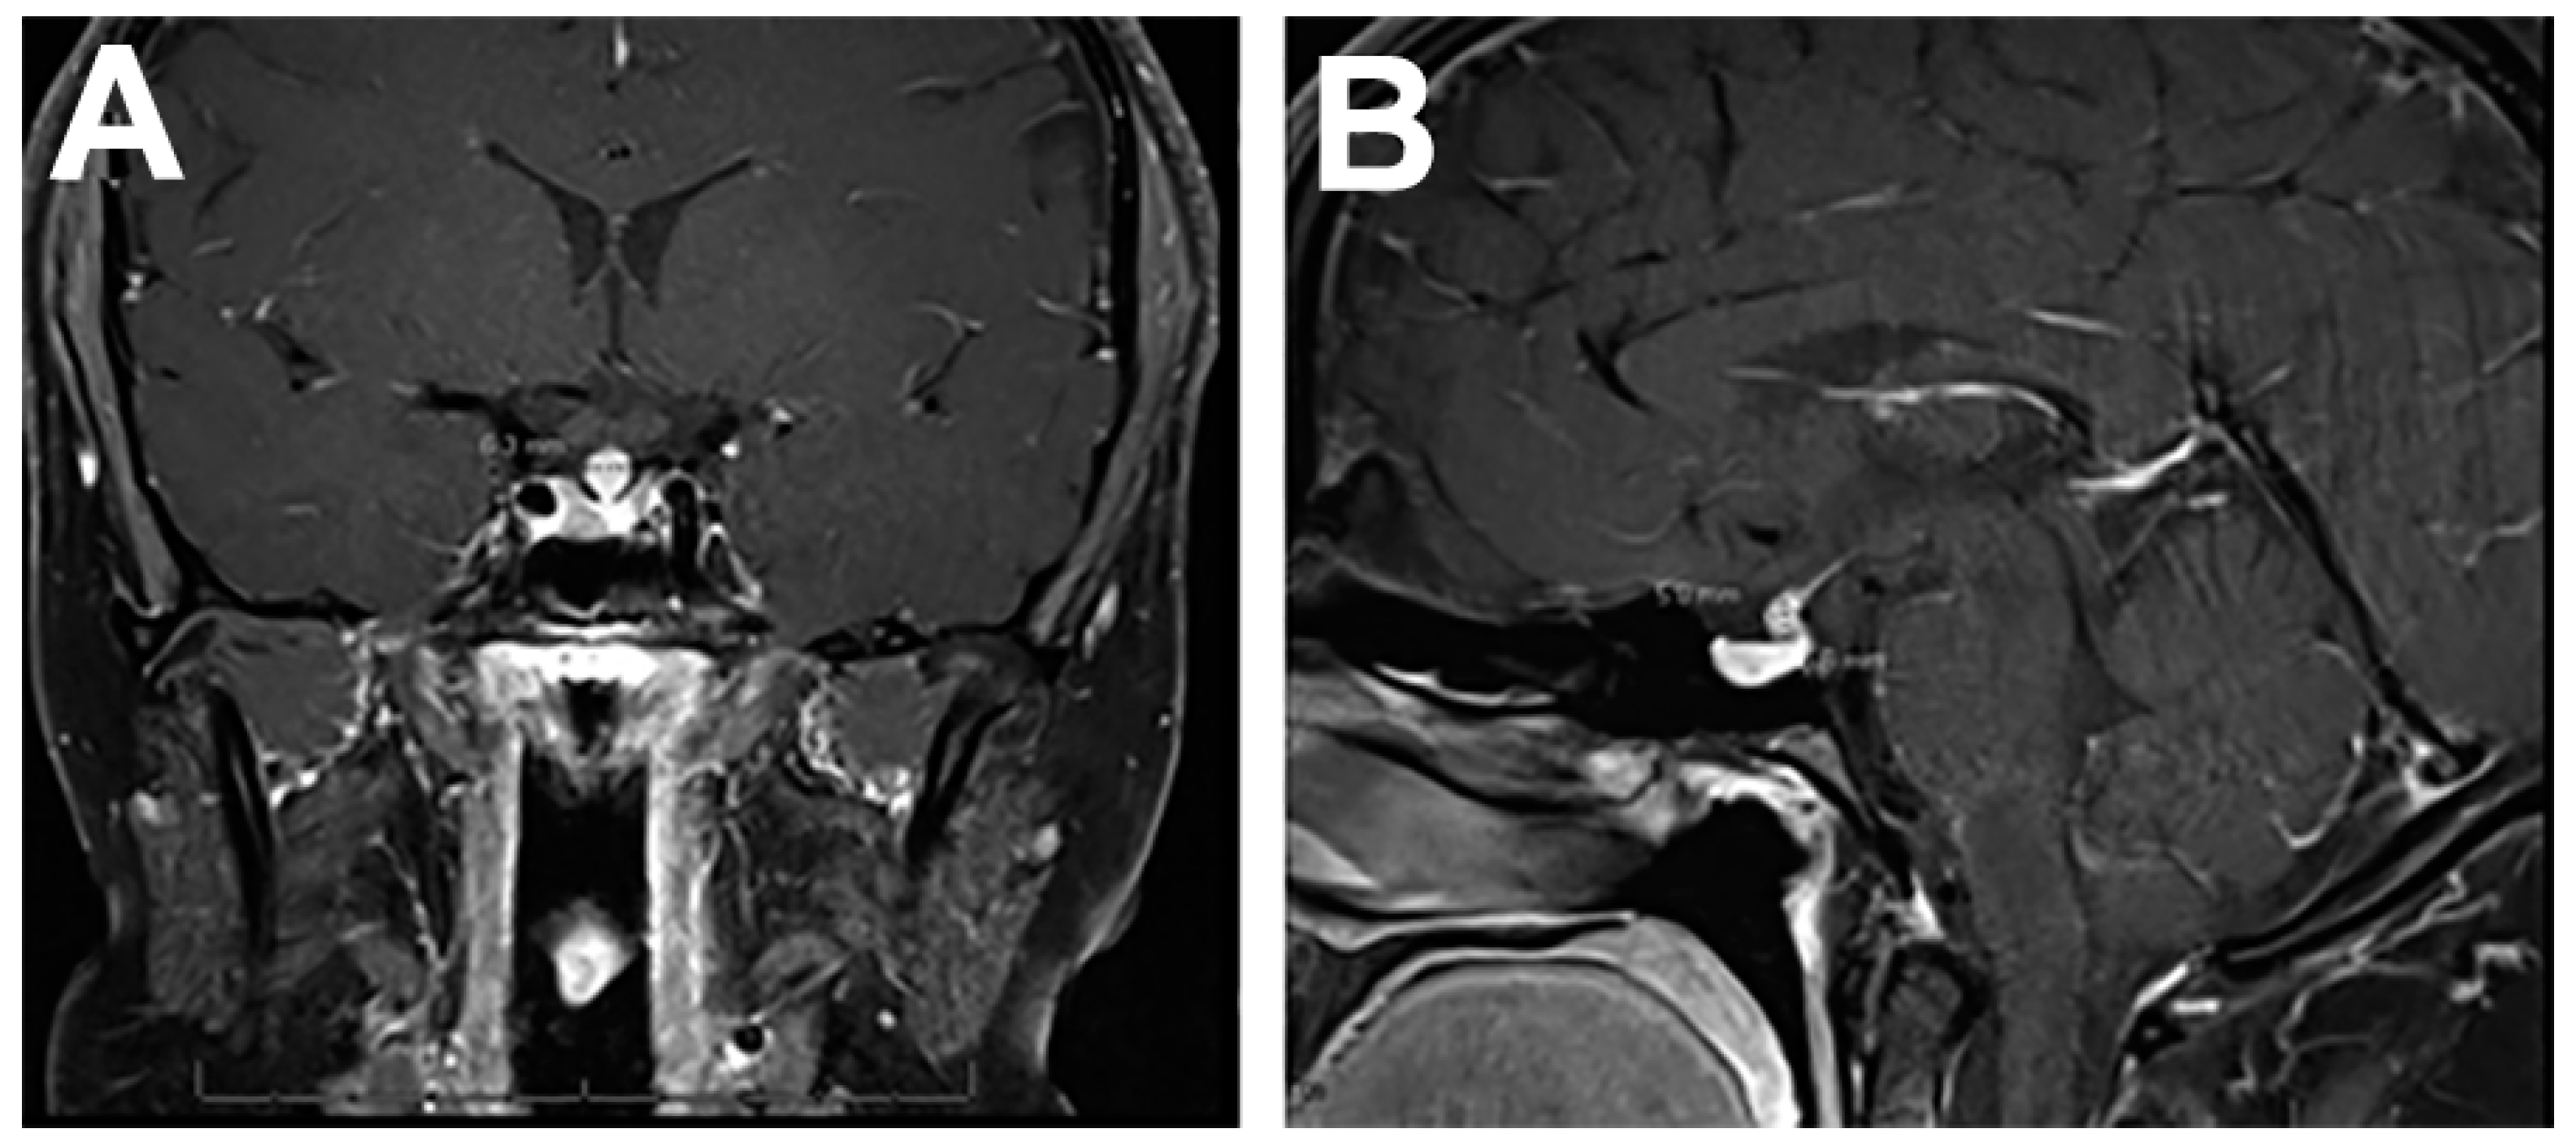

4.1. Imaging Features